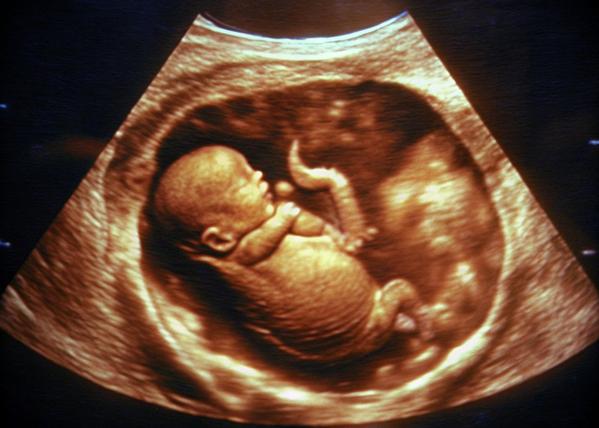

Painless Normal and Caesarean Delivery in Nashik – Supporting Safe and Comfortable Births

Painless Normal and Caesarean Delivery in Nashik has become an important consideration for expecting mothers who want both safety and comfort during childbirth. Fear of pain often overshadows the excitement of pregnancy, but modern obstetric care focuses on informed preparation and gentle support.

At Bagul Nursing Home and Dr. Bagul’s Hope IVF Center in Nashik, delivery planning begins well before the due date. Mothers are guided through pain management options, delivery methods, and medical indications that influence whether a normal or caesarean delivery is advised. Clear explanations help families feel prepared rather than anxious.

Painless delivery techniques are carefully administered by experienced teams, ensuring comfort without compromising maternal or fetal safety. For caesarean births, attention is given to post-delivery recovery, mobility, and emotional reassurance. Each birth plan is shaped around medical needs and personal comfort, not assumptions.